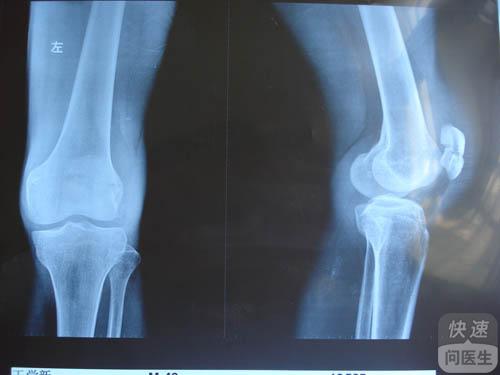

核心提示:胫骨内髁骨软骨病,又称胫骨内翻或Blount病。是指胫骨内髁软骨发育不良而产生的膝内翻畸形。本病好发于黑人儿童,主要表现为弓形腿。跟着小编去认识一下关于胫骨内髁骨软骨病的相关知识吧。一、胫骨内髁骨软骨病...